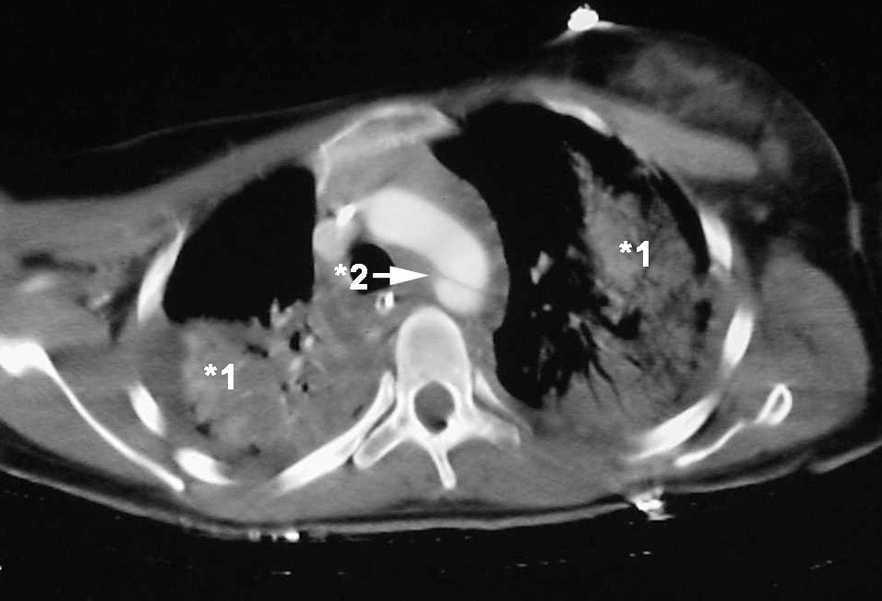

Mujer de 21 años sin antecedentes de interés que presenta politraumatismo tras accidente de tráfico. La paciente es recogida con Glasgow de 15 puntos precisando intubación y conexión a ventilación mecánica por insuficiencia respiratoria. En la tomografía axial computarizada (TAC) torácica de ingreso presenta contusión pulmonar bilateral (*1, fig. 1) y una imagen de "flap" intimal, a 2 cm de la salida de la arteria subclavia izquierda, de morfología irregular y con aumento de calibre compatible con rotura traumática de aorta torácica (*2, fig. 1). En la reconstrucción de la TAC también se aprecia dicha imagen de rotura traumática de aorta (fig. 2). Se procedió de manera urgente a la colocación por vía femoral de prótesis aórtica endovascular con buen resultado final.

Figura 1